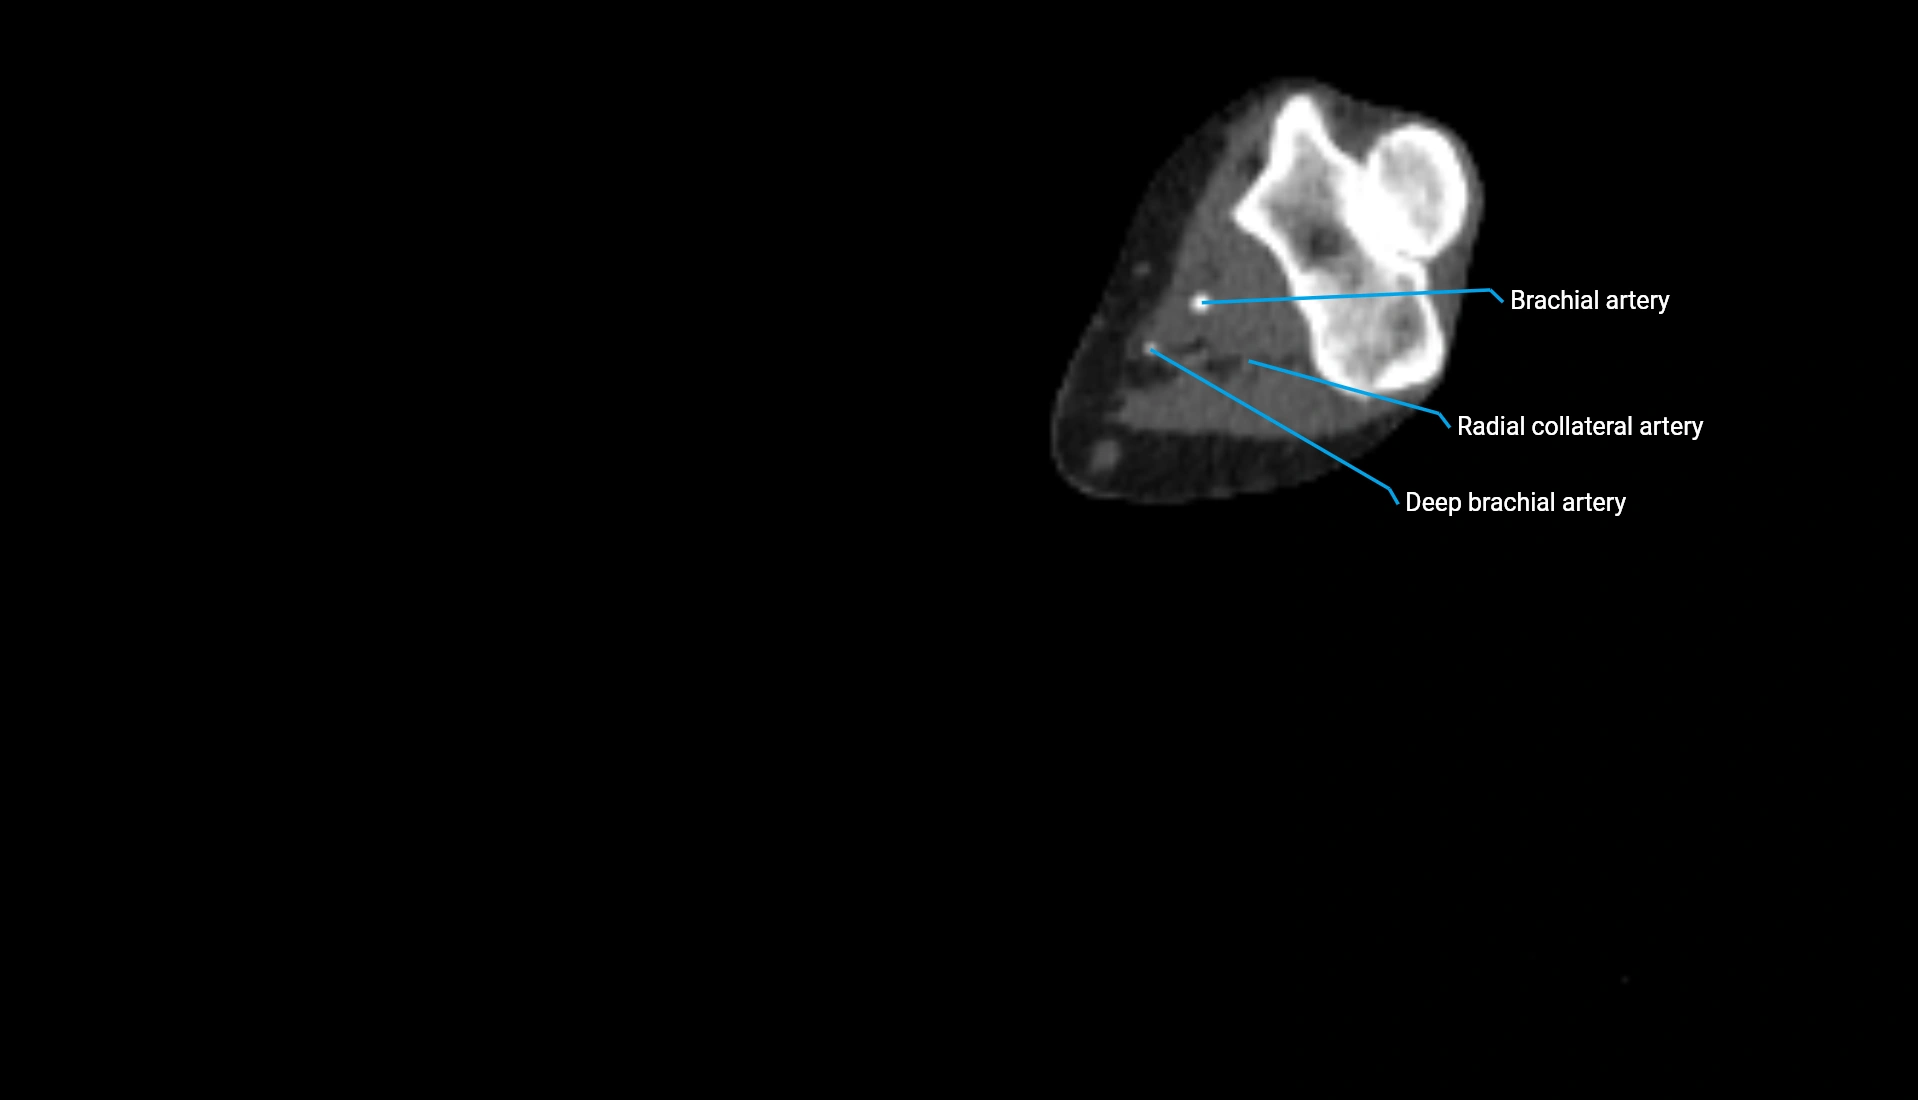

CT Appearance

Non-Contrast CT:

• Cortex: High-density, sharply defined

• Subchondral bone: Dense cancellous matrix

• Articular surface: Smooth concave contour articulating with the capitellum

• Excellent for evaluating bone integrity, alignment, and subtle fractures

Post-Contrast CT:

• Bone: No enhancement

• Joint capsule and synovium: Mild enhancement outlining the joint

• Improves contrast between soft tissues and bony margins

• Useful in detecting subtle joint abnormalities or postoperative changes